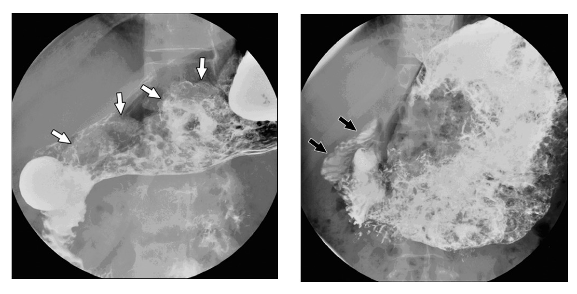

第一个原因当然是胃的大小。根据宾夕法尼亚大学发表在《美国放射学期刊》(American Journal of Roentgenology)上的一篇文章,职业大胃王在实验室的 X 光机前用“令人叹为观止的、毫无停顿的速度”进食热狗时,松弛的胃袋会逐渐涨大,基本占满了被试者的上腹部。在食用了 36 根热狗后,研究人员描述该大胃王的肚子从外观上看“会让人有一种宫内妊娠的错觉”。作为对照组的普通人则完全没有表示出这种现象。因此,大胃王之所以为大胃王,并不是因为他们可以将吃下的东西更快地研磨、加工、排出,而是因为他们拥有名副其实的“大胃”装万物。

正常人(左)与大胃王(右)进食后的胃 X 光片对比。图片来源:论文